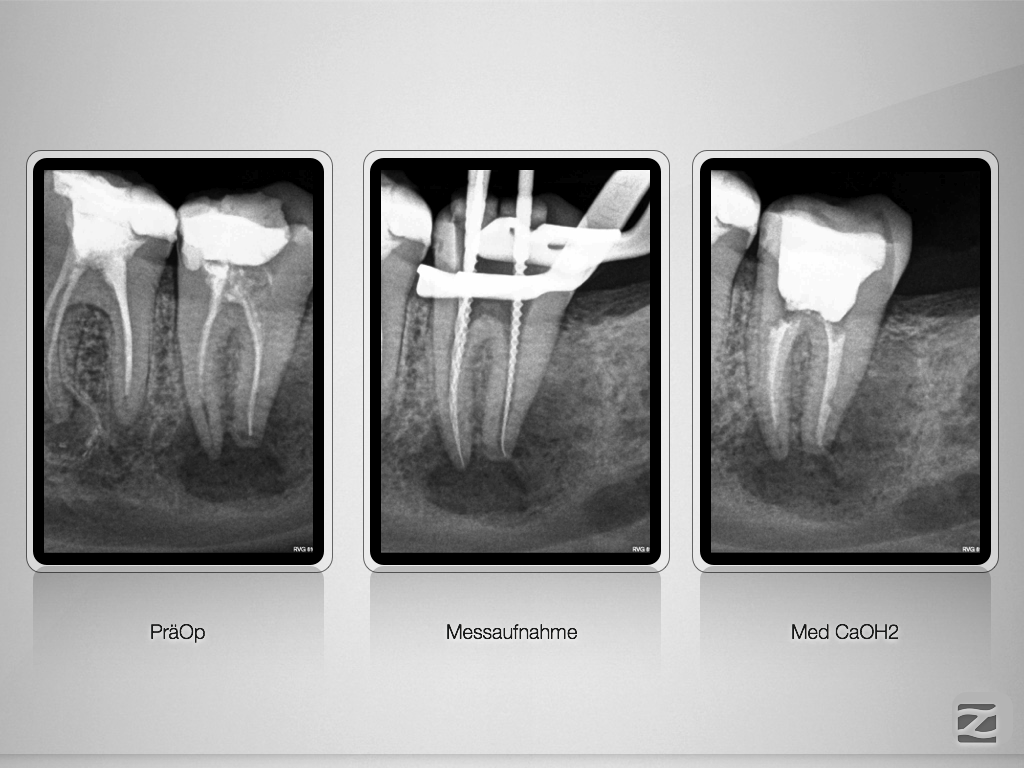

37D.008

Ausgedehnte apikale Lyse